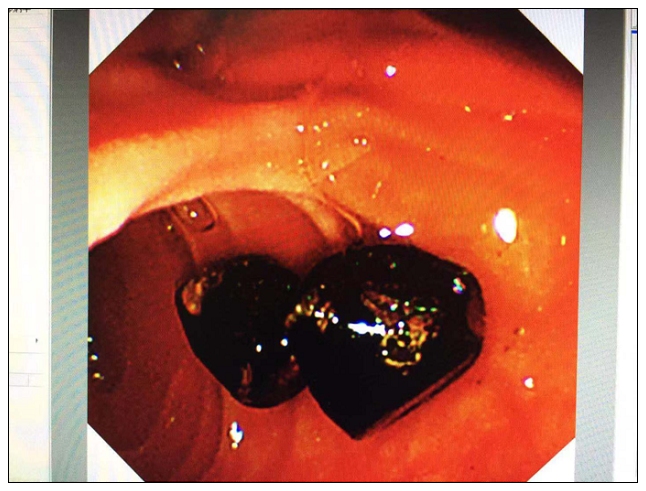

患者王某,79岁,因剑突下疼痛在外院反复治疗效果不佳。由于患者年龄大,既往有“高血压、冠心病、脑梗”等病史,同时有“心脏起搏器置入”及“胆囊手术”病史,都是传统手术的种种障碍。患者听家里亲戚说市人民医院有一种不用开刀也可以把石头取出来的办法,遂来我院就诊。针对该患者这一特殊情况,手术小组经过充分的术前准备、评估,顺利为患者取出了两枚1.2*1.0cm、1.0*1.0cm结石,解除患者多年的病痛,大幅提高患者生活质量。